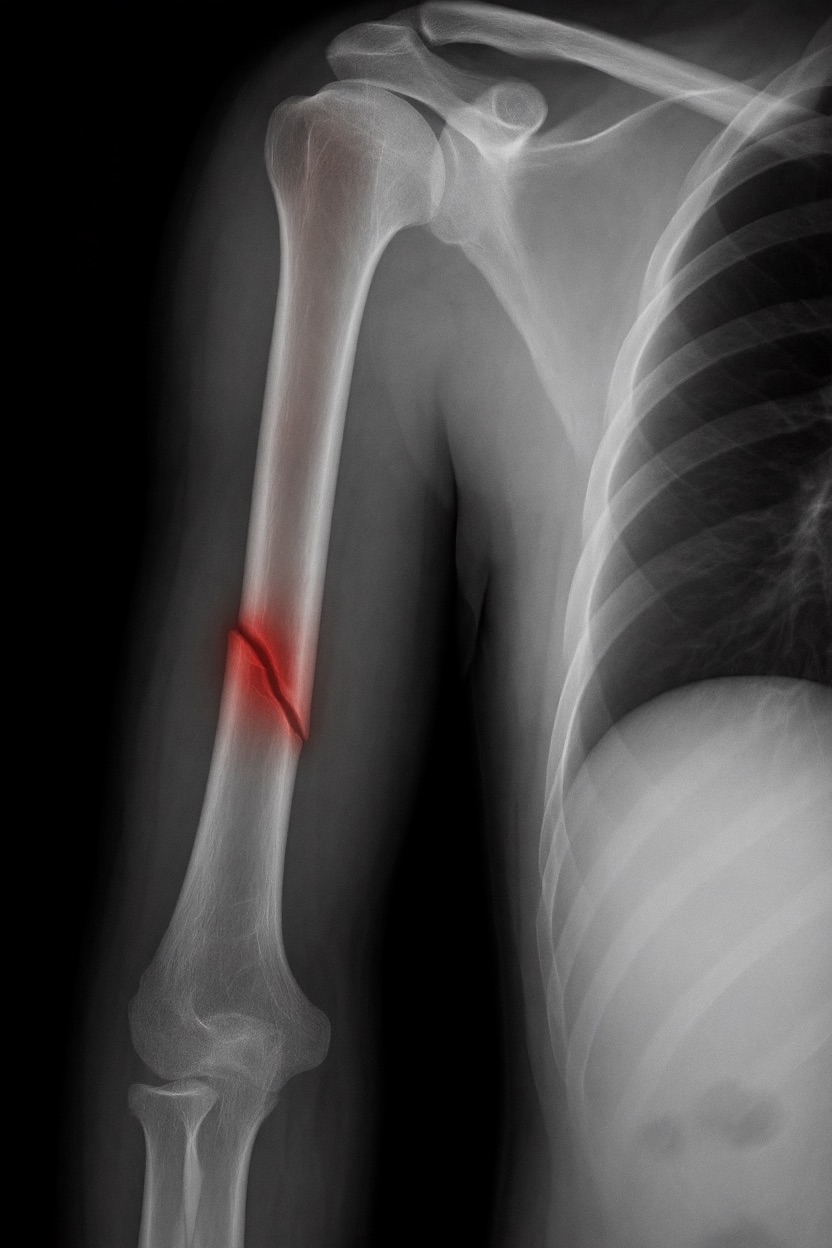

アートや写真の編集用に設計されたFlux Kontextのようなモデルを、医療画像、たとえば「単純な」骨折の赤色マーキングに使用できるか?

即答:面白い結果を出すが、過剰に反応し、医療ツールとしては信頼性に欠ける。これはアイデアを試すためのプロトタイプに過ぎない。

テスト結果:

- 偽陽性 ≈ 24%

- 骨折検出 ≈ 20%

感度モード(検出を優先、ノイズ多め)

- Euler、15ステップ、Karras

- Denoise:1.0

結果:

- 偽陽性 ≈ 80%

- 骨折検出 ≈ 86%

さらに攻撃的な設定(例:rk beta57、Denoise 1.0)では、**偽陽性100%、検出100%**という馬鹿げた結果に:すべてを赤で塗りつぶし、健常部もほぼすべて骨折と誤認する。未経験の目には区別がつかない。

Civitai用に作成した、100% AI生成の合成ミニデータセット(健康なX線10枚、骨折のあるX線10枚)でテスト:

- 健康な骨での偽陽性:100%

- 骨折検出:≈ 45%